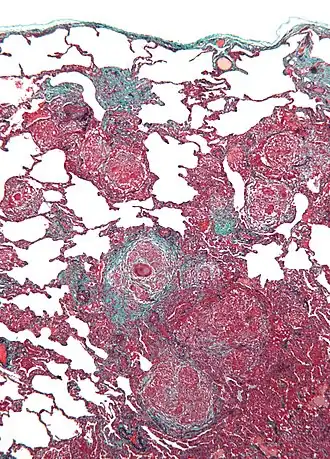

Biopsie de poumon.

La PHS aiguë se caractérise par la formation de granulomes non-caséeux et une infiltration interstitielle de cellules mononucléaires à distribution péribronchique avec une prédominance de cellules géantes[3].

La forme subaiguë, ou intermittente, se manifeste plus souvent par des granulomes bien limités, non caséeux, une bronchiolite avec ou sans pneumonie systématisée, et fibrose interstitielle[3].

Les formes chroniques présentent des signes supplémentaires d'inflammation chronique interstitielle et de destruction alvéolaire (images en rayons de miel) associés une fibrose dense. Des dépôts linéaires de cholestérol ou des corps radiés sont présents à l'intérieur ou en dehors des granulomes[3].